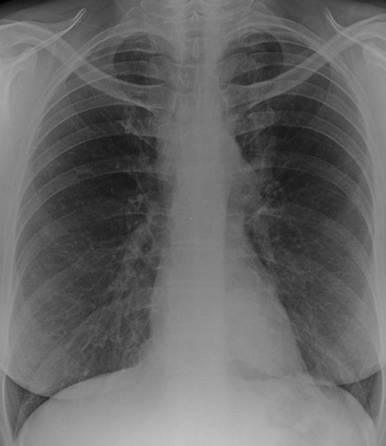

Figure 1. Normal chest X-ray two months earlier. |

Figure 2. Chest X-ray showed mediastinal mass. |